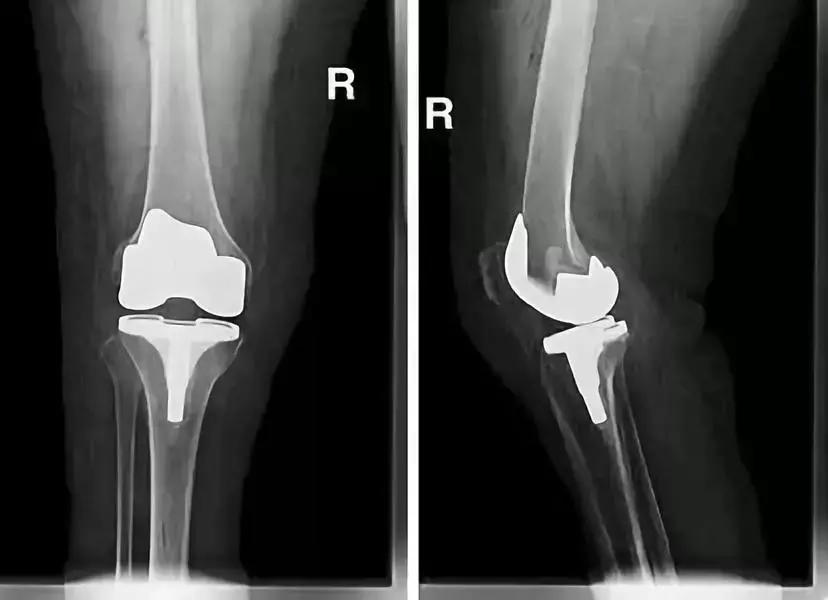

人工关节形成新的关节摩擦面,彻底避免了骨头磨骨头,也松解了关节僵硬,应该说是解除后期骨关节炎患者膝关节疼痛的最有效方法。

关节置换置换手术

现在的人工关节材料和技术已经非常成熟,通常认为55岁以后适合关节置换,60到75岁是最佳置换年龄。然而,是否手术越迟,结果就越好呢?我不以为然。对每个具体病人而言,生理年龄比实际年龄更重要,身体好、生理年龄小(虽然实际年龄已达60岁)的病人手术时间确实可适当推迟。。

随着病人年龄增长,心肺功能只会每况愈下,如果有手术指征,可以考虑适当提早手术,这样不仅减少手术风险,也使患者可以早日行走锻炼,促进心肺功能的康复。